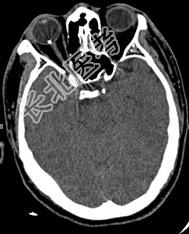

- [材料题] 患者男性,4岁,以“右眼外伤后视物不清8天”为主诉入院。眼部检查:右眼视力指数/0cm,左眼视力.0。右眼混合充血,角膜透明,KP(+),6点钟方位角膜缘可见2mm裂伤口,已闭合;前房中等深度,房水闪光(+);虹膜表面纹理清晰,无前后粘连,6点钟方位可见穿通孔;瞳孔圆,直径3mm;晶状体混浊;眼底无法窥视。左眼未见明显异常。眼眶X线检查结果见图155,CT检查结果见图156(平扫)和图157(三维成像)。

图156